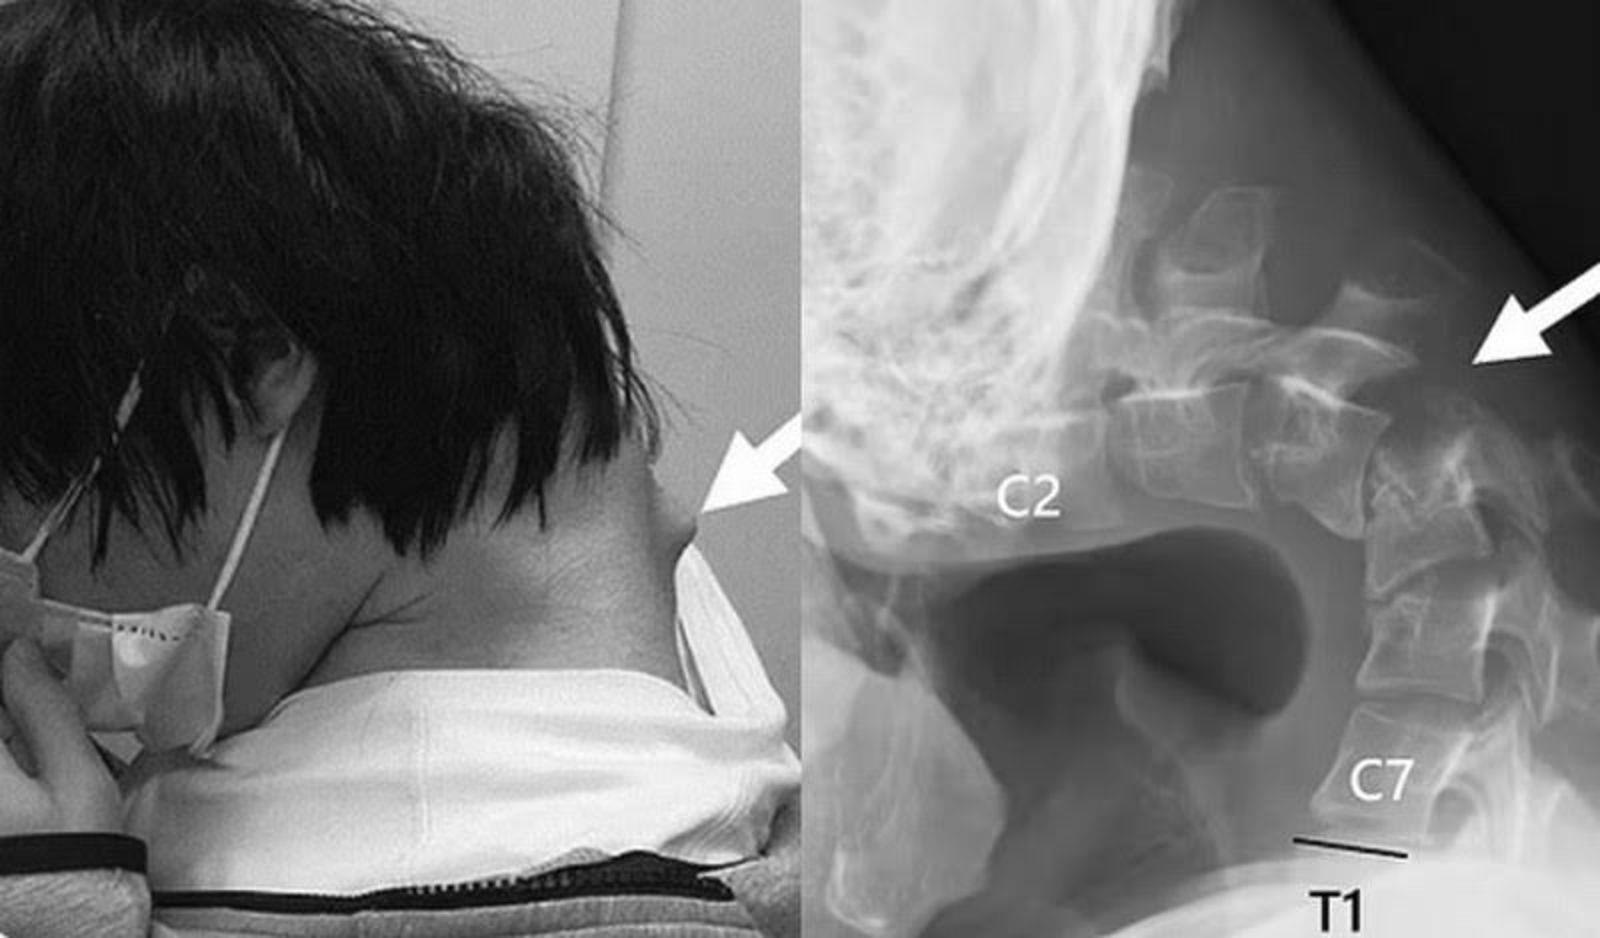

日本一名年輕男子因長期低頭玩遊戲,導致頸椎變形。(圖/翻攝自 X @scharacter123/鏡週刊)

別再當低頭族!日本一名25歲年輕人因長期沉迷手機遊戲,造成頸部肌肉嚴重退化,不僅難以抬頭,吞嚥困難,就連頸部也異常出現角狀突起物。

醫療團隊表示,該名男子青少年時期慘遭霸凌,使他封閉自己,輟學後常年躲在房間裡沉迷於手機遊戲,長時間低頭玩遊戲,逐漸與社會隔絕。醫療團隊進行影像檢查後發現,該名男子的頸椎出現變形和位移,甚至長了一個腫塊,確診罹患「頭部下垂症候群」(Dropped Head Syndrome)。醫師判斷,這是因為他的椎骨處於不自然的位置,導致「過度伸展」所致。